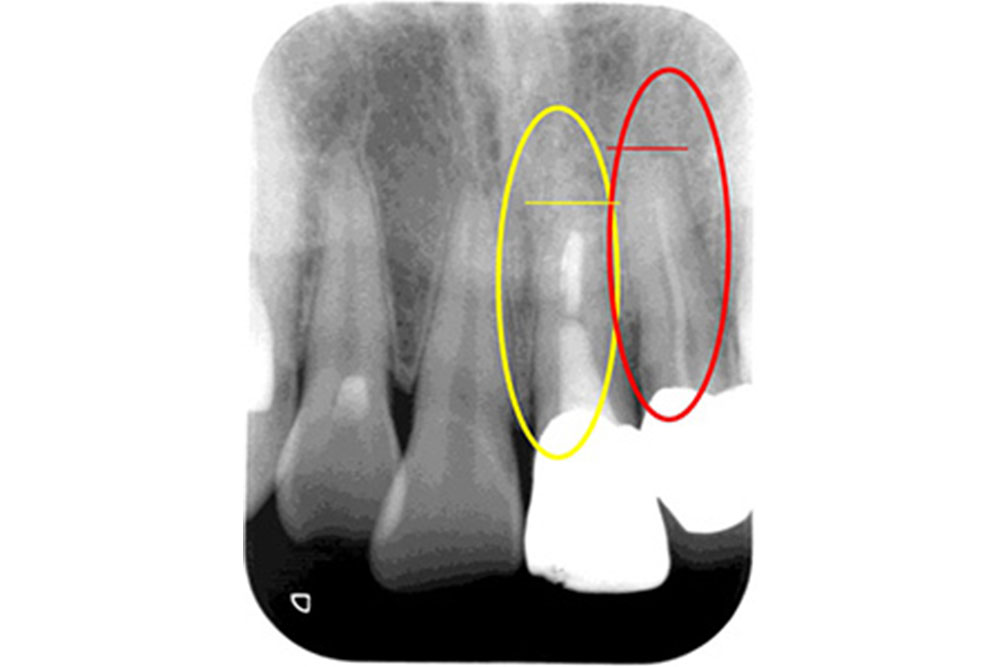

空洞に挟まったハリを除去することが可能

過去に他の医院で治療した際の折れたハリ(赤丸)が入っているレントゲン。

ハリを除去し、徹底的に洗浄したレントゲン。

空洞を根の先までしっかり埋めたレントゲン。

根の治療はハリを使用するため、ハリが折れて空洞の中に挟まってしまうケースがあります。これは治療の特性上、どうしても起こりうることなのですが、隙間を埋めることができずに空洞があると、しっかり洗浄されていないため、そこが痛み始めたらどうすることもできません。しかし、当院ではその根の中の細かい空洞に挟まったハリを除去し、治療することが可能です。ある患者様が半年以上もジンジンする痛みに悩まされ、いくつかの医院に行かれたそうですが治せる医院がなく、諦めかけていたそうです。しかし、当院にお越しいただいてハリを除去し治療を行ったところ、3回の通院のみで痛みを完全になくすことができました。